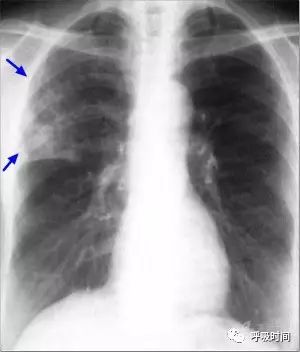

图 11 肺纤维化病变影——弥漫性特发性肺间质纤维化。双肺胸膜下可见网状影及条索影(蓝箭头)